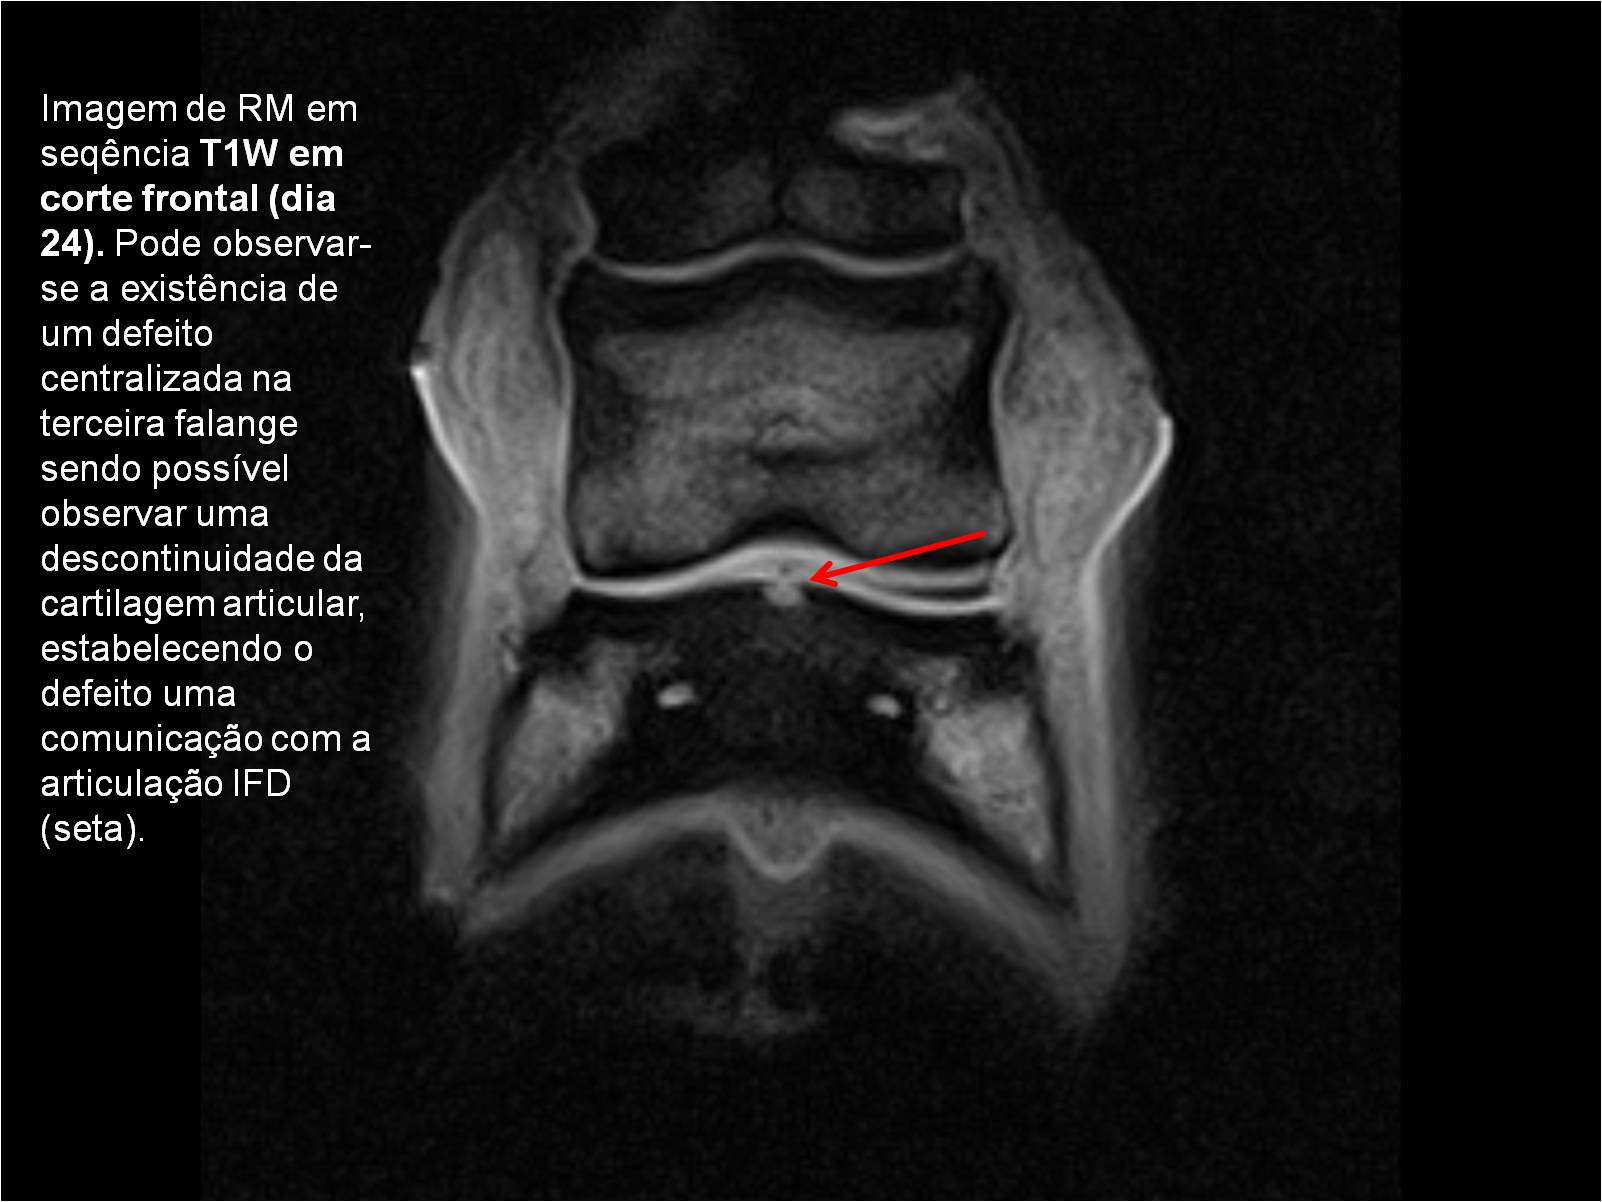

Publisher: Universidade de Évora

Abstract: O relatório de estágio encontra-se estruturado em três partes distintas. A primeira parte faz a caracterização das infraestruturas e funcionamento do Hospital Veterinário de Equinos de Lüsche, Oldenburg, Alemanha, assim como a análise casuística dos casos clínicos acompanhados durante os 6 meses de estágio. A segunda parte consiste de uma revisão bibliográfica sobre quistos do osso subcondral em equinos. Por fim, a terceira parte consta da apresentação e discussão de um caso clínico, nomeadamente o diagnóstico e acompanhamento imagiológico, por ressonância magnética, de um quisto subcondral na terceira falange num cavalo adulto; ### Abstract Equine Practice- Subcondral bone cyst of the third phalanx This internship report is divided in three parts. The first part characterizes the infrastructure and function of the Equine Hospital Lüsche, Oldenburg, Germany, as well as the casuistic of the clinical cases accompanied during the 6 month internship. The second part consists in a bibliographic review of cystic lesions of the subchondral bone in equines. The third part consists in a case report, the diagnostic and imagiological accompaniment, by use of magnetic resonance imaging, of a subchondral bone cyst in the distal phalanx of an adult equine.